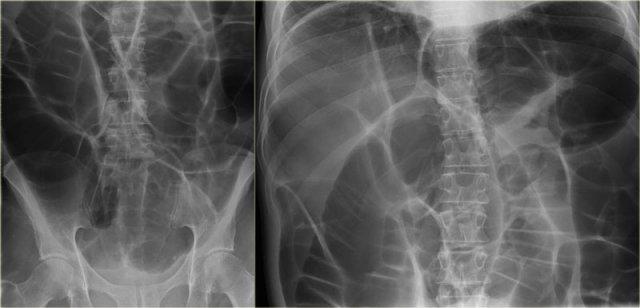

Bên trái là hình ảnh X-quang bụng thẳng của một nam bệnh nhân 57 tuổi với tiền sử đau bụng và chướng bụng tăng dần trong hai ngày.

Hãy quan sát hình ảnh trước rồi tiếp tục.

Ngoài hình ảnh giãn ruột lan tỏa, dấu hiệu chính trên phim này là một cấu trúc chứa khí lớn ở vùng chậu.

Chẩn đoán quan trọng cần nghĩ đến là xoắn đại tràng, và nhiều người sẽ chẩn đoán đây là xoắn đại tràng sigma do vị trí nằm ở vùng chậu.

Tuy nhiên, đây thực chất là xoắn manh tràng như sẽ được giải thích bên dưới.

Các hình X-quang cho thấy hình ảnh điển hình của xoắn manh tràng.

Lưu ý rằng quai ruột giãn hướng về phía vùng xoắn, đây là vị trí mà manh tràng thường nằm.